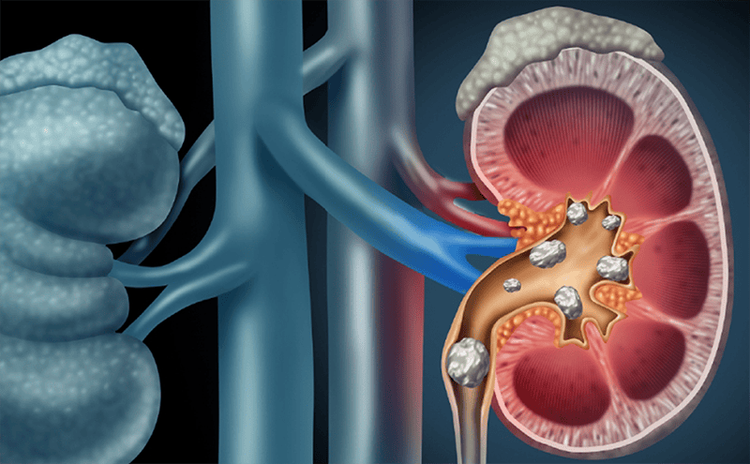

Hình ảnh niệu đồ tĩnh mạch có thể được sử dụng để chẩn đoán các rối loạn ảnh hưởng đến đường tiết niệu, chẳng hạn như sỏi thận, sỏi bàng quang, tuyến tiền liệt phì đại, nang thận hoặc khối u đường tiết niệu.

- Sỏi thận: Được chỉ định đối với những loại sỏi không cản quang hoặc khó khảo sát trên phim X – quang thông thường, sỏi trong thận và niệu quản thường hiển thị rõ trên niệu đồ tĩnh mạch.

- Sỏi bàng quang

- Nang thận

- Khối u đường tiết niệu

- Rối loạn cấu trúc thận, chẳng hạn như thận bọt biển – một dị tật bẩm sinh của các ống nhỏ bên trong thận